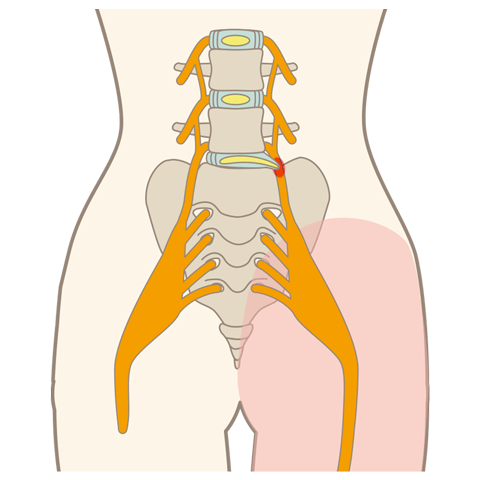

坐骨神経痛

坐骨神経痛とは、腰椎椎間板ヘルニアや腰部脊柱管狭窄症などを原因とし、腰から下部の臀部や脚部に痛みや痺れを感じる症状です。